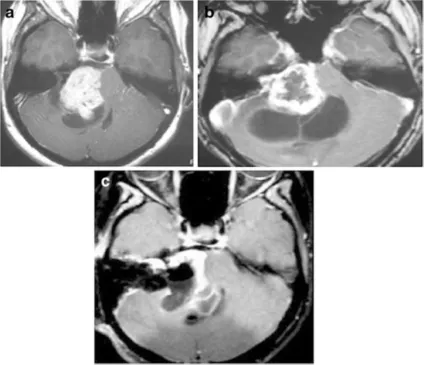

还有个29岁的年轻女性,放疗后8个月,肿瘤的囊性部分急剧扩大,虽然尝试了囊肿穿刺引流,但没有改善。随后她逐渐失去听力、无法行走,只能坐轮椅。手术中医生发现,肿瘤包膜和脑干严重粘连,只能做次全切除。

图2 :a增强后轴向核磁共振显示右侧中等大小的肿瘤,不均匀强化压迫脑干。肿瘤具有实体和囊肿部分(在直线加速器治疗之前)。b增强后轴向MRI显示肿瘤实体部分轻微生长,囊性部分增大(直线加速器治疗后8个月)。肿瘤缺乏中央强化。c术后增强轴向MRI显示肿瘤的一小部分残留